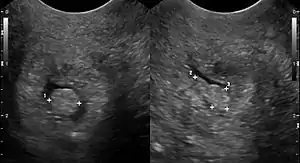

| Cervical polyp on ultrasound | |